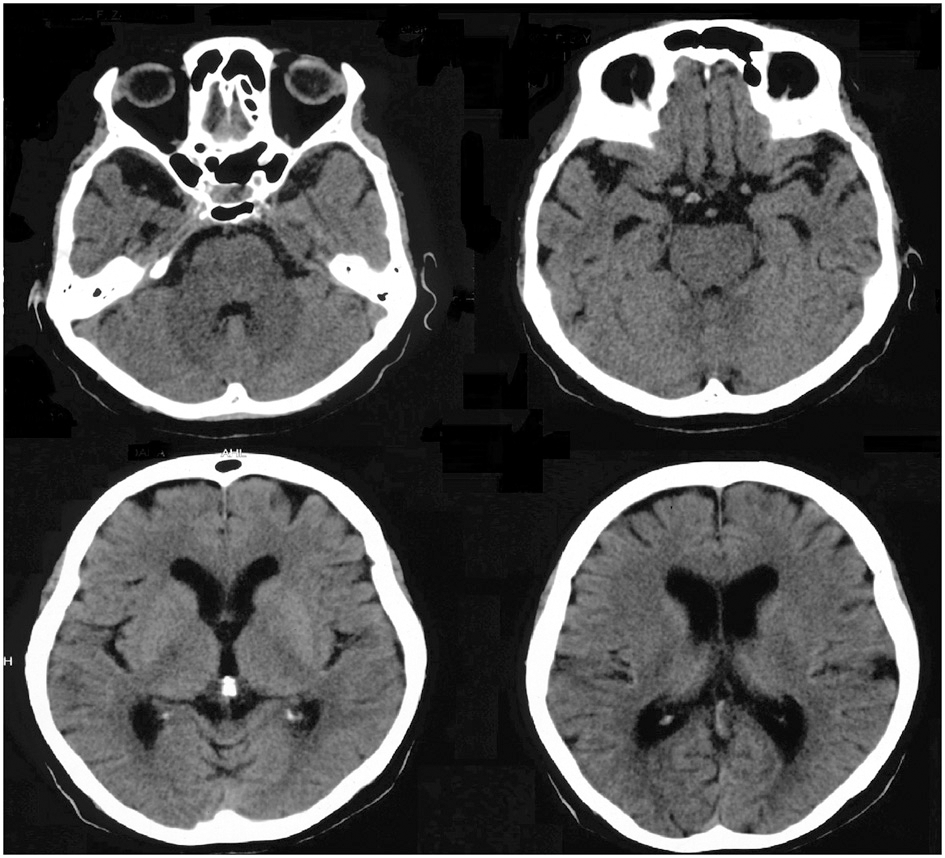

The standard neurological examination was normal, without eye movement disorders or extrapyramidal signs. Formal neuropsychological evaluation (November 2010—Table 3) showed an impairment in global cognitive efficiency both on the Mini-Mental State Exam (MMSE: 16/30; Folstein et al., 1975) and on the Mattis Dementia Rating Scale (103/144; Porto et al., 2003). Executive tasks such as DRS initiation/perseveration subscale, FAS letter fluency and digit span were altered. There was a marked episodic memory deficit, which was characterized by low performance on both learning and delayed recall tasks from the Rey Auditory Verbal Learning Test (Malloy-Diniz et al., 2007) and in the DRS memory subscale. There was a moderate impairment in the naming task (9/15; Bertolucci et al., 2001). The visual abilities assessed using the Visual Object and Space Perception Battery (Warrington and James, 1991; Quental et al., 2013) were preserved (number location and cube analysis). The patient had no deficit on gesture execution, and no signs of Balint or Gertsmann syndromes. Brain computed tomography scanning in 2009 showed a remarkable atrophy in temporopolar regions bilaterally and a mild frontal polar atrophy (Figure 1). Brain MRI performed 2 years later showed no signs of cerebrovascular disease and confirmed the same regional atrophy pattern with additional diffuse brain shrinkage. On clinical follow-up after 36 months, the global cognitive efficiency assessed using MMSE remained stable (see Table 4), although language and functional abilities deteriorated, as assessed using the Functional Activities Questionnaire (Pfeffer et al., 1982). The diagnosis of probable bvFTD was retained on a clinical basis.

Figure 1. Brain computed tomography scan performed in 2009 showing marked atrophy in bilateral temporopolar and frontal regions.